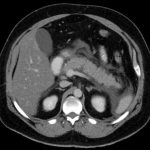

Carcinoma pancreatico metastatico-Immagine TC assiale con contrasto iv. Adenocarcinoma macrocistico della testa pancreatica. Credito: pubblico dominio-